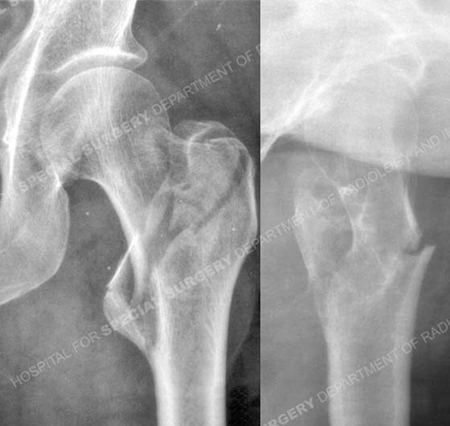

Anteroposterior and lateral radiographs revealing an unstable intertrochanteric fracture.